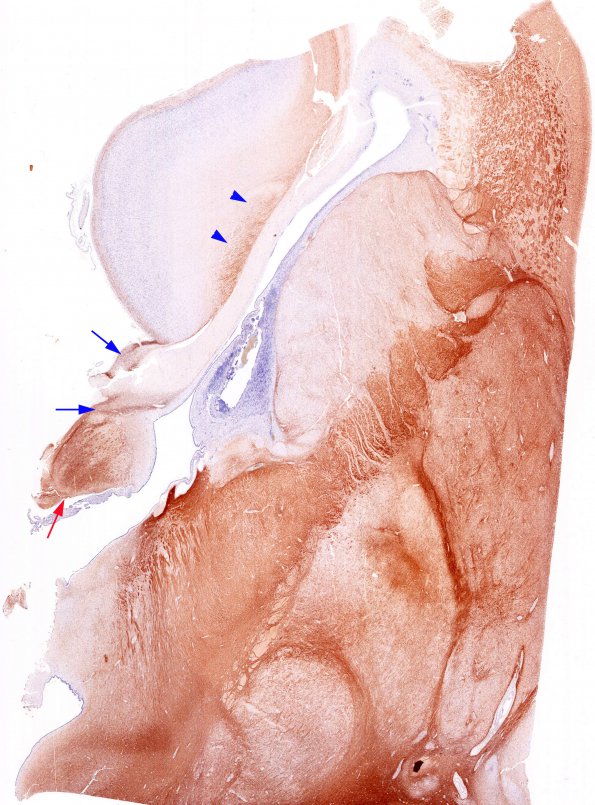

Washington University Experience | DEVELOPMENTAL MALFORMATIONS | Agenesis - Corpus Callosum | 10A3 Agenesis of Corpus Callosum in hyperglycinemia (Case 10) N11 NF

Questionable case of agenesis of the corpus callosum is suspicious for artificial postmortem rupture of the corpus of a soft neonatal brain. Examination with whole mount histologic sections shows a thinned corpus and loss of transverse running axons. Staining for neurofilaments is complex (images #10A3,10A4). The red arrow (#10A3) is most consistent with fornix and the blue arrows identify possible Probst bundles, seen at higher magnification in images #10A4, #10A5. Axons directed transversely, as might be expected if a normal corpus was artificially torn during dissection, are not identified.